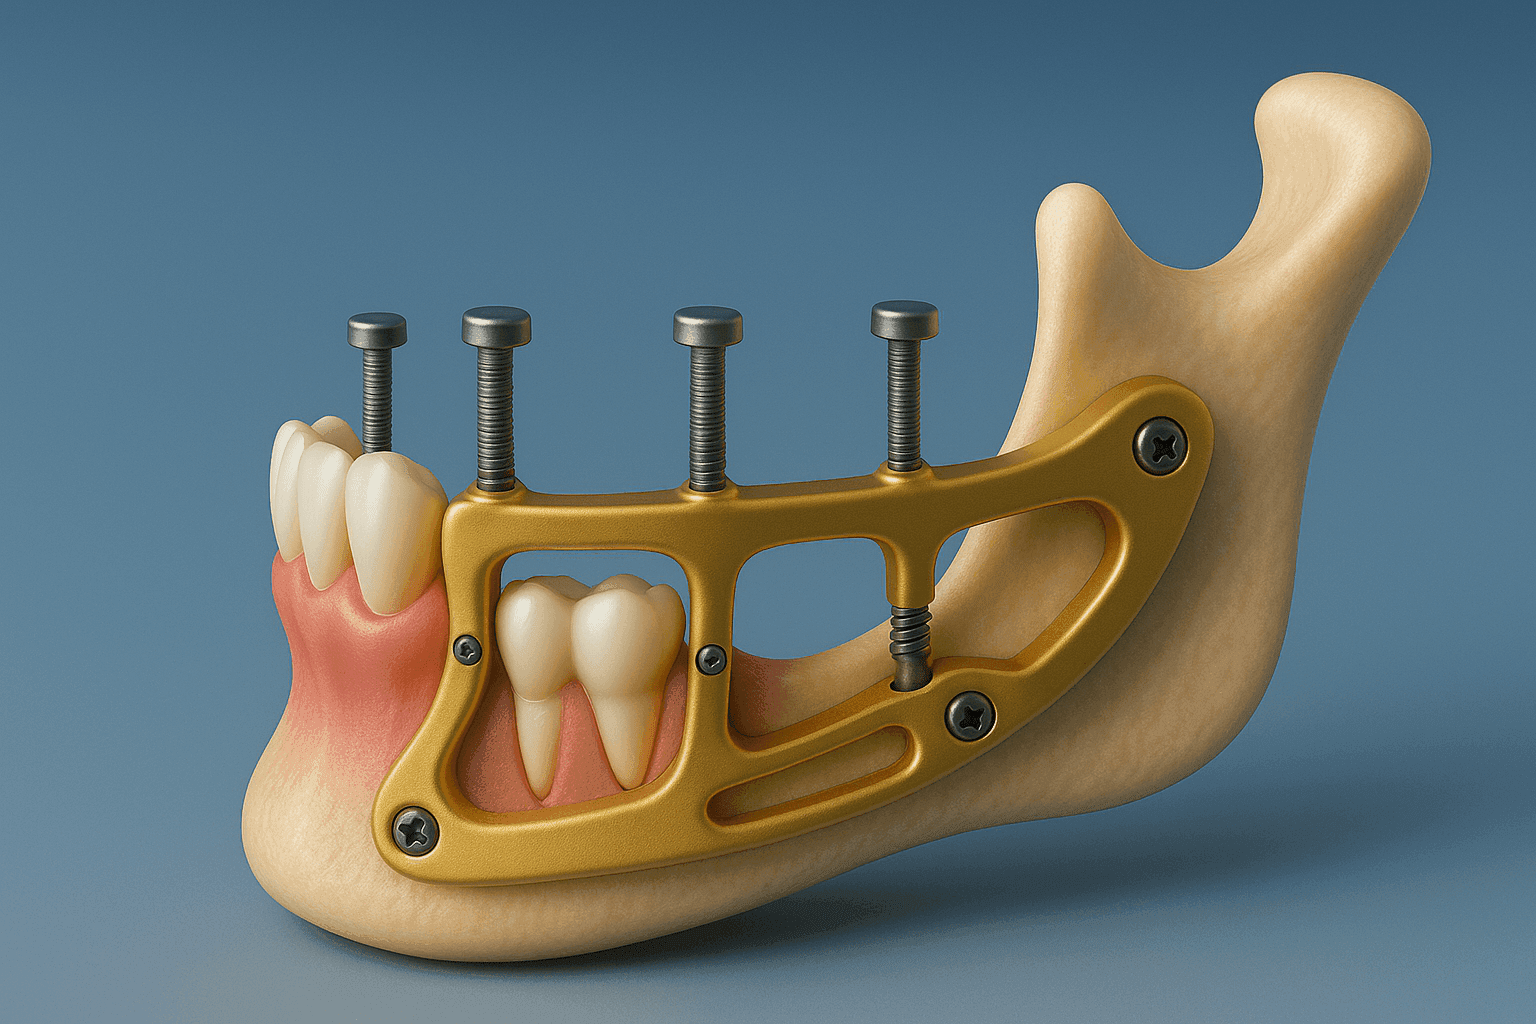

Implantes subperiósticos y técnica Admodum: solución para pacientes sin hueso

Descubre la técnica de implantes totales (Admodum) y cómo pueden transformar para siempre la sonrisa de pacientes sin o con poco hueso

Hoy en día, el área de la implantología dental debe incluir la tecnología para respaldar los diagnósticos y asegurar los mejores tratamientos para los pacientes de implantes dentales.